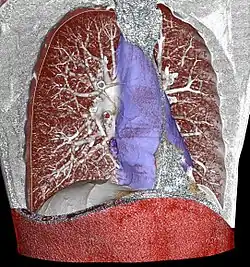

Acute mediastinitis can be confirmed by contrast x-rays since most cases of acute mediastinitis are due to esophageal perforation. Other studies that can be used include endoscopic visualization, Chest CT scan with oral and intravenous contrast.

With regards to CT Imaging, the extent of involvement of the mediastinum can be evaluated. Therefore, acute mediastinitis can be classified into three categories:[9]